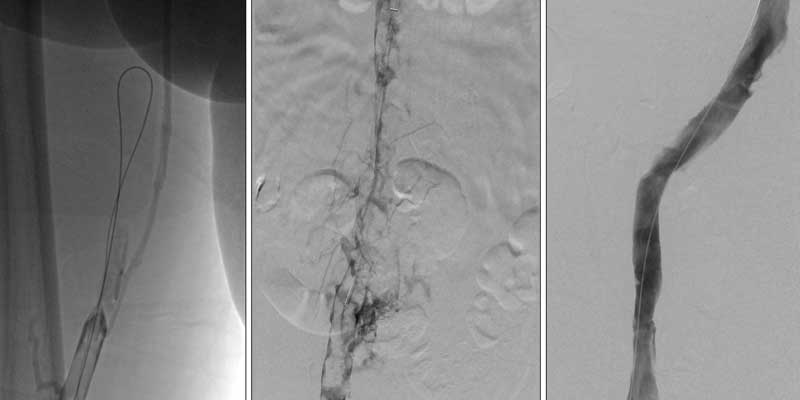

IVC (Inferior Vena Cava) Filter Placement and Pulmonary Artery Mechanical Thrombectomy are minimally invasive procedures used to prevent and treat serious blood clot–related conditions. An IVC filter is placed in the main vein returning blood from the lower body to prevent clots from reaching the lungs, while mechanical thrombectomy involves removing clots directly from the pulmonary arteries to restore blood flow.

IVC filter placement involves deploying a filter through a catheter to trap clots before they reach the lungs. Pulmonary artery mechanical thrombectomy uses specialized devices to physically remove clots from the lung arteries, improving oxygenation, reducing strain on the heart, and stabilizing critically ill patients.